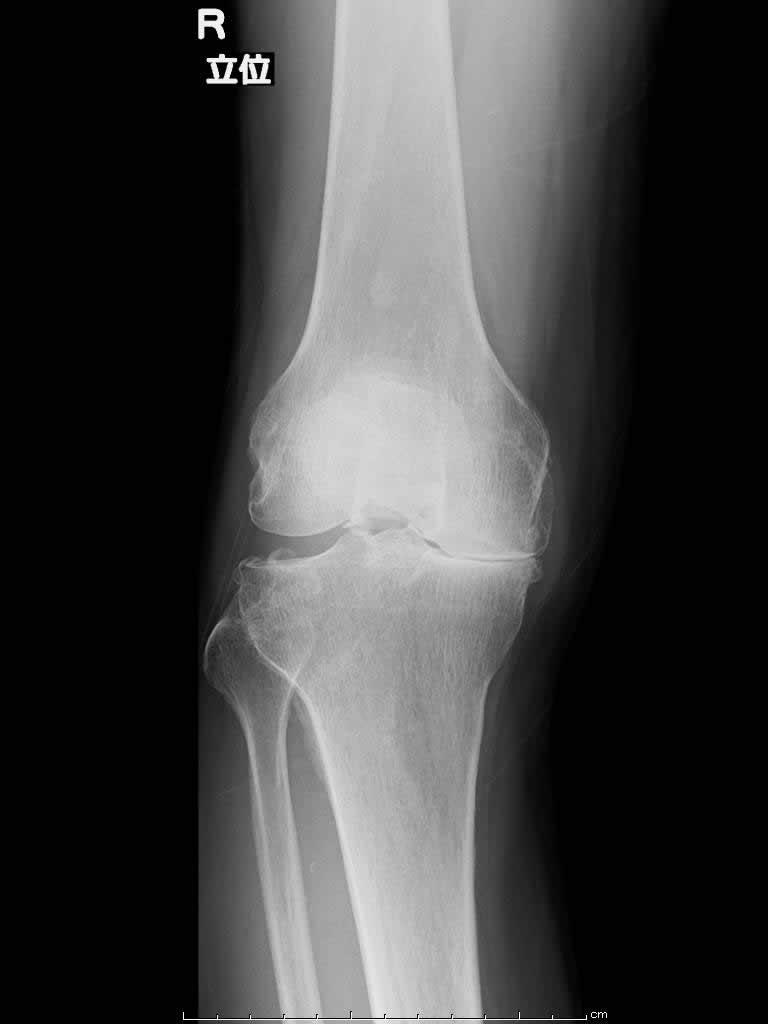

人工膝関節置換術(TKA)(変形性膝関節症)

加齢や怪我などにより、傷んだ軟骨と骨を削って、人工関節に置き換えます。

※内外の両側の軟骨が傷んだ方が適応となります。

【術前】